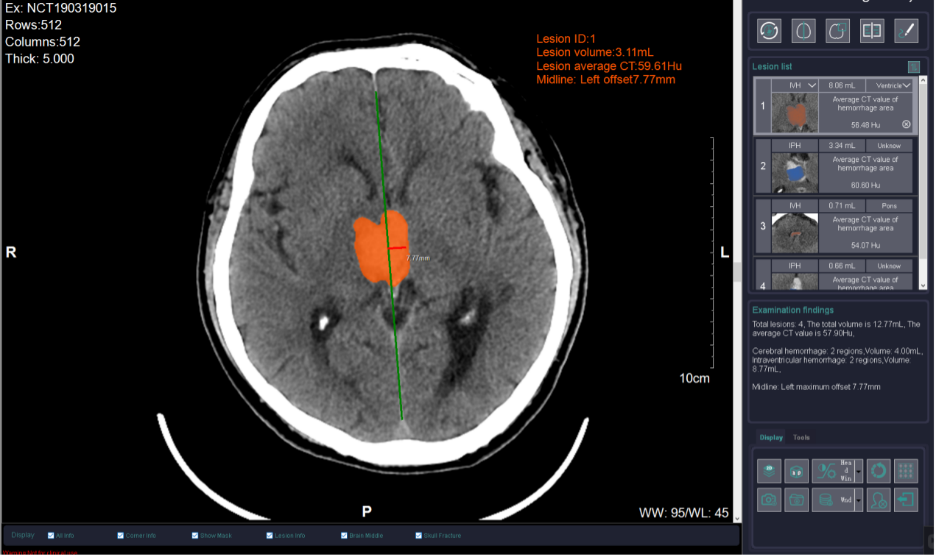

Consider the treatment of head trauma, for instance. While both epidural and intracerebral hematomas are types of intracranial hematomas, they actually differ in location, causes, symptoms, and treatment principle. Thus, making an accurate distinction between them are absolutely critical for treatment. The CT scan machine can provide precise localization and clear boundary images of each type of hematoma (the error margin of less than one millimeter). This precise imaging allows physicians to quickly assess the severity of the injury. It directly guides the critical decision between conservative management and emergency surgery, preventing any dangerous delays that stem from diagnostic uncertainty.